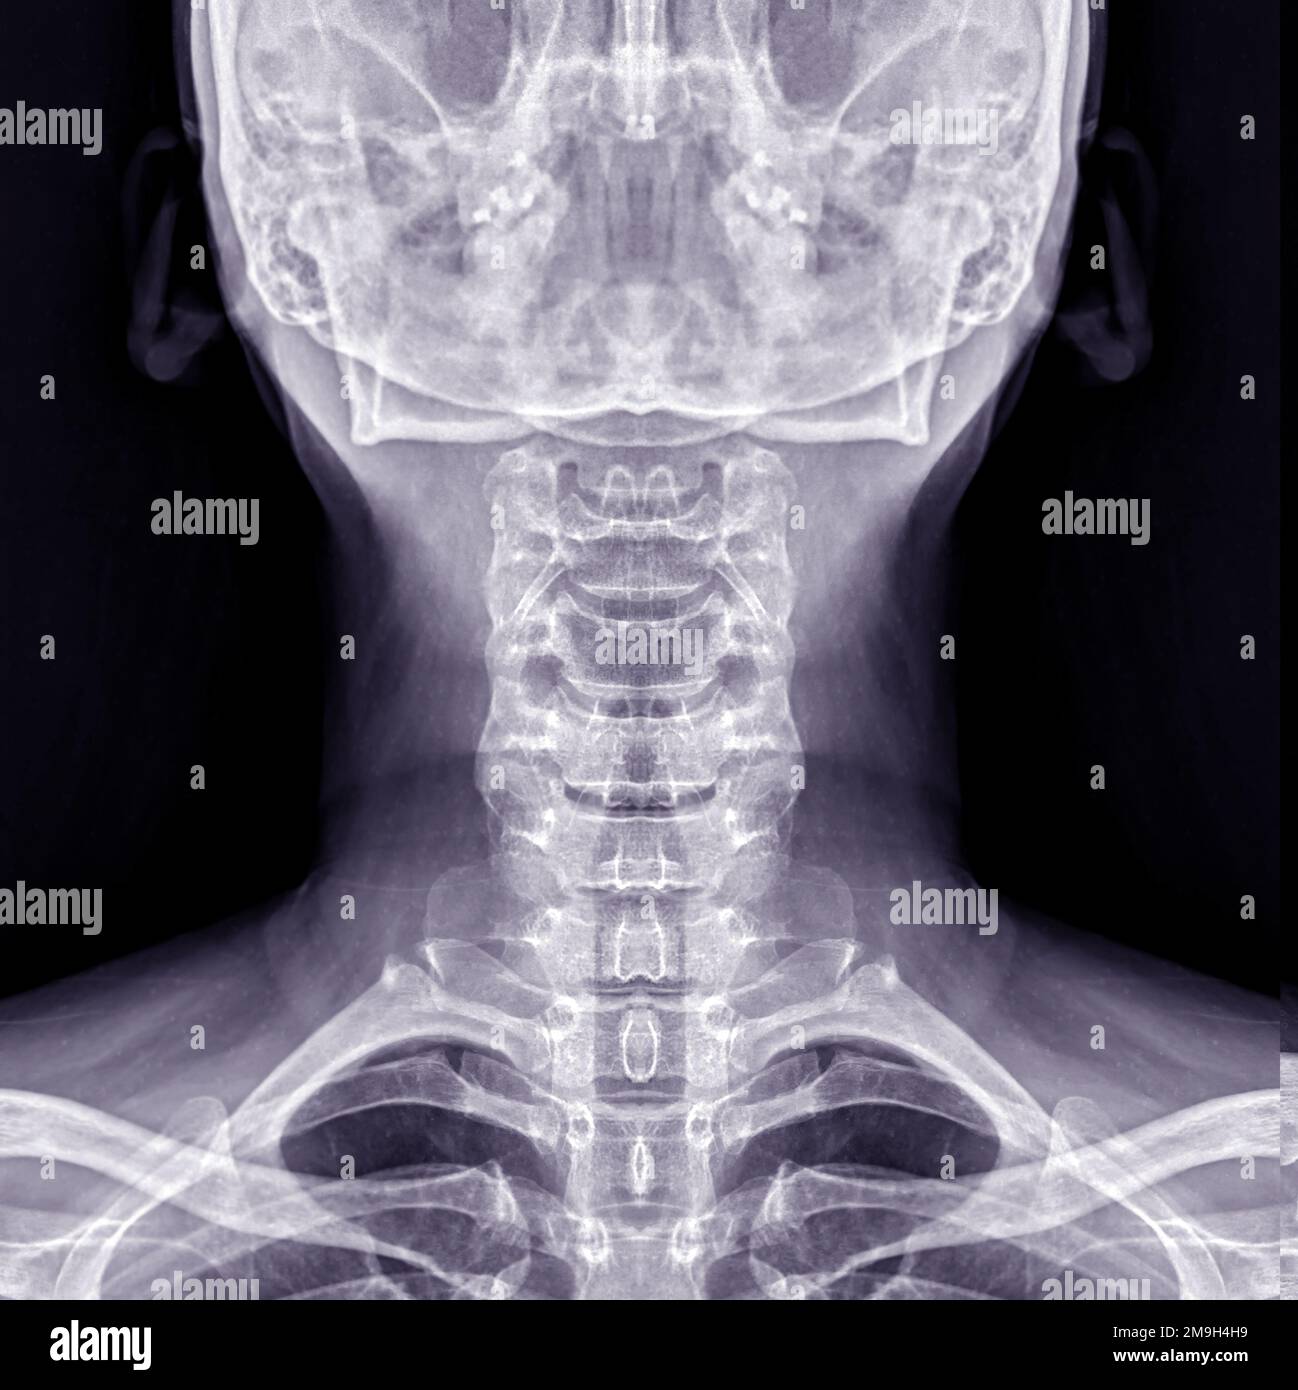

Hipertrofia De Adenoides Grado II En La Nasofaringe De Un Niño. Una Imagen De La Columna Cervical. Vertical Fotos, retratos, imágenes y fotografía de archivo libres de derecho. Image 140017831